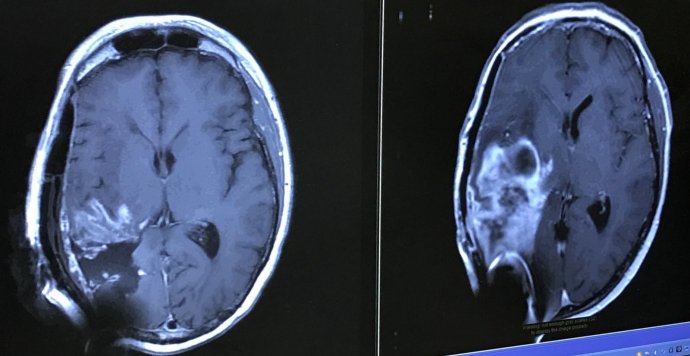

The diagnosis was terminal brain cancer. Hargobind will go through eight surgeries to remove tumor re-growth, add a shunt to drain fluids from his brain to the stomach and have a artificial skull inserted. One of these surgeries last year included a trial therapy utilizing an injection in the brain. He came out of surgery without the use of the left side of the body.